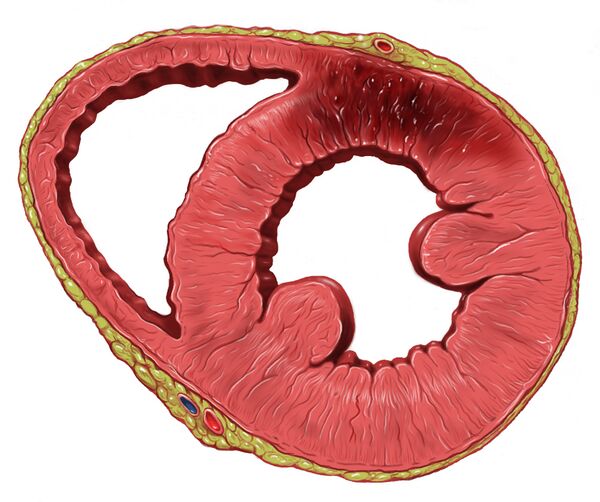

Инфаркт миокарда чаще развивается в левом желудочке или межжелудочковой перегородке, и крайне редко — в правом желудочке или предсердиях. Типичен белый инфаркт с геморрагическим венчиком: омертвевший участок имеет неправильную форму и может располагаться под эндокардом, эпикардом или охватывать всю толщу миокарда. Характерно образование фибринозных отложений на перикарде и тромботических — на эндокарде[5].